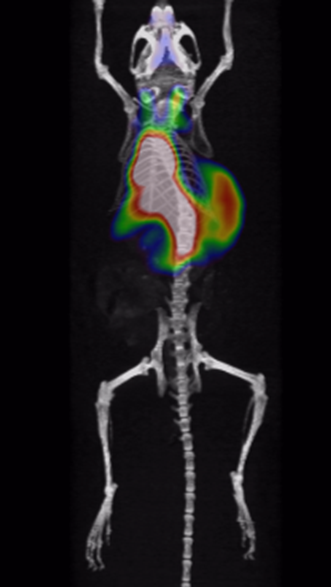

It has been proved that Cu-64-marked nanoantibodies are well-targeting for tumors, with high local uptake and long retention